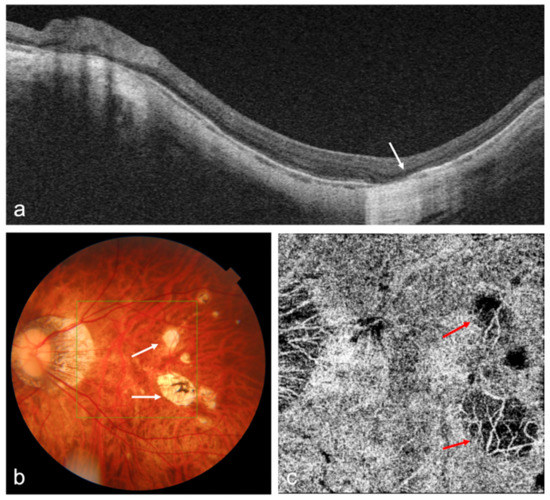

Advances in OCT Imaging in Myopia and Pathologic Myopia

Advances in imaging with optical coherence tomography (OCT) and optical coherence tomography angiography (OCTA) technology, including the development of swept source OCT/OCTA, widefield or ultra-widefield systems, have greatly improved the understanding, diagnosis, and treatment of myopia and myopia-related complications. Anterior segment OCT is [...] Read more.

Advances in imaging with optical coherence tomography (OCT) and optical coherence tomography angiography (OCTA) technology, including the development of swept source OCT/OCTA, widefield or ultra-widefield systems, have greatly improved the understanding, diagnosis, and treatment of myopia and myopia-related complications. Anterior segment OCT is useful for imaging the anterior segment of myopes, providing the basis for implantable collamer lens optimization, or detecting intraocular lens decentration in high myopic patients. OCT has enhanced imaging of vitreous properties, and measurement of choroidal thickness in myopic eyes. Widefield OCT systems have greatly improved the visualization of peripheral retinal lesions and have enabled the evaluation of wide staphyloma and ocular curvature. Based on OCT imaging, a new classification system and guidelines for the management of myopic traction maculopathy have been proposed; different dome-shaped macula morphologies have been described; and myopia-related abnormalities in the optic nerve and peripapillary region have been demonstrated. OCTA can quantitatively evaluate the retinal microvasculature and choriocapillaris, which is useful for the early detection of myopic choroidal neovascularization and the evaluation of anti-vascular endothelial growth factor therapy in these patients. In addition, the application of artificial intelligence in OCT/OCTA imaging in myopia has achieved promising results. Full article